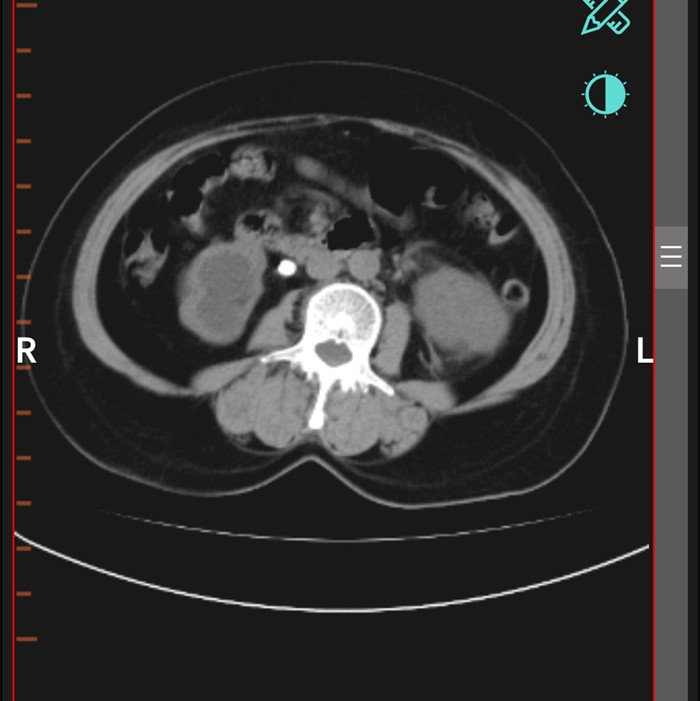

柴女士,62歲,北川縣擂鼓鎮(zhèn)人,因腰右側(cè)疼痛難忍,她來到北川羌族自治縣人民醫(yī)院就診,經(jīng)檢查提示,柴女士右輸尿管上段結(jié)石嵌頓引起重度腎積水。

“要及時解除梗阻,可以行腹腔鏡輸尿管切開取石術(shù)取代開放手術(shù)。”在朱劍勇的帶領下,這支剛剛成立的“泌尿外科團隊”,僅用了一個半小時就完成了手術(shù)?!案骨荤R輸尿管切開取石術(shù)創(chuàng)傷小,患者腰腹部只有3個戳孔,術(shù)后恢復快?!敝靹τ抡f。